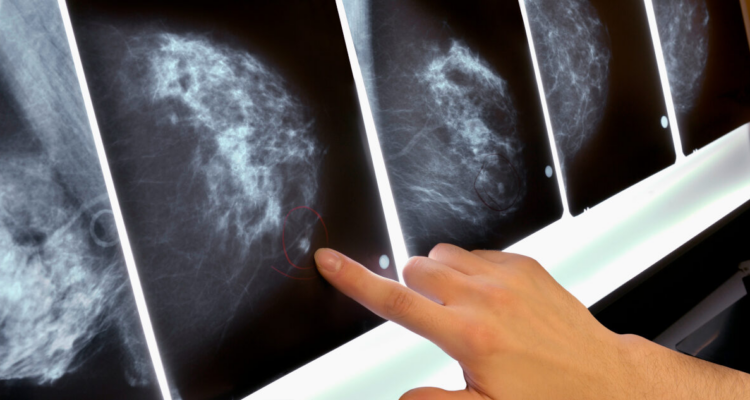

El servicio que debía entregar Novakimen era exámenes ginecológicos y mamografías a mujeres derivadas desde los cesfam, los que eran realizados por facultativos sin especialidad, siendo los resultados certificados con las firmas de radiólogos que no trabajaban en el centro médico.

El caso más grave es el de una mujer cuyo examen en Novakimen arrojó un resultado que descartaba cualquier enfermedad, pero que tras repetirlo en otro laboratorio confirmó un cáncer.